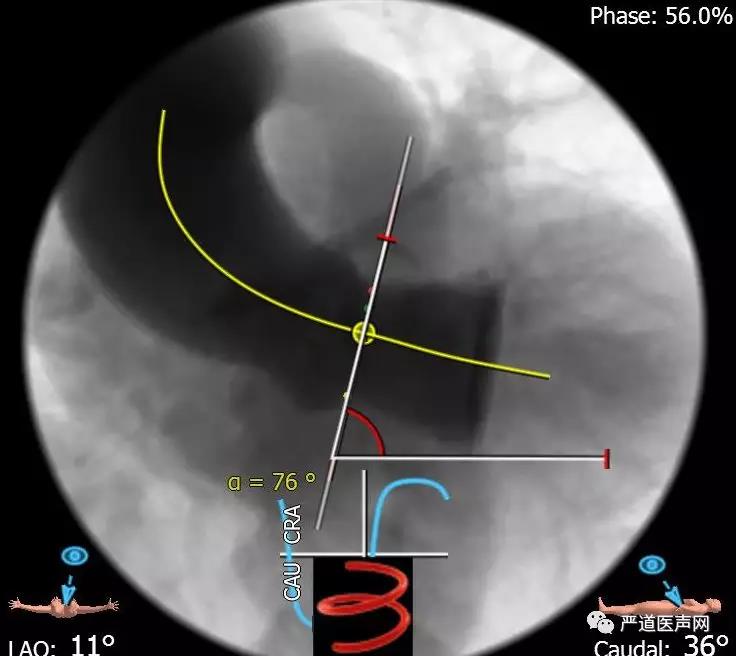

术前分析,主动脉瓣二叶瓣畸形及重度钙化

术前分析显示,主动脉高度的迂曲

轨道建立后,顺利的进行了球囊的扩张,这时到了最关键的时刻,Venus Plus 瓣膜的输送和释放,而恰巧这个时候镜头切向了会场。在国外,术者们对如此高难度手术往往束手无策,所以主持人和现场的观众都兴致饶饶的看着中国专家的场上表现。果然,瓣膜运送的阻力非常大,尤其是通过迂曲的主动脉弓风险更大,周玉杰教授在每一步前进的过程中都要感受到前进所遇到的阻力,除了避免瓣膜损害主动脉弓外,助手也要密切配合,任何一个配合不良的动作,都会增加导丝刺破心脏的风险,此外为保障瓣膜的同轴性,还需要借助一个网篮作为牵引,将瓣膜送至了合适的位置。